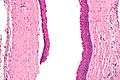

The definitive diagnosis is by histologic analysis, i.e. excision and examination under the microscope.

Under the microscope, KCOTs vaguely resemble keratinized squamous epithelium;[3] however, they lack rete ridges and often have an artifactual separation from their basement membrane.

High mag.